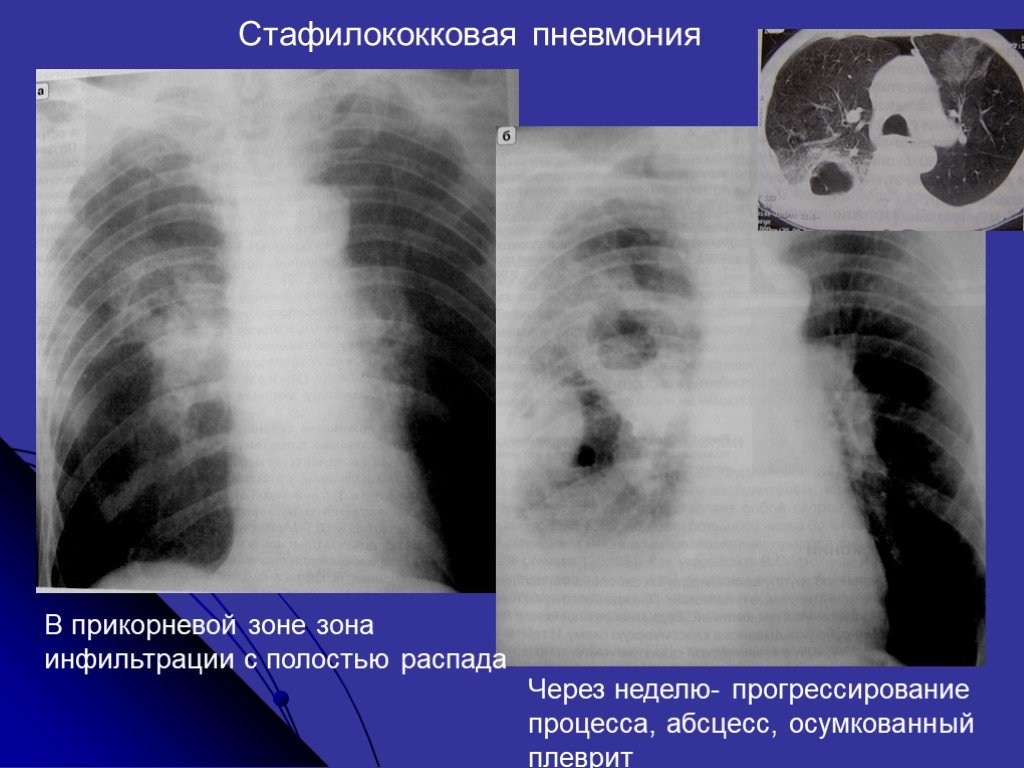

Бактериальная деструкция легких у детей презентация - 88 фото